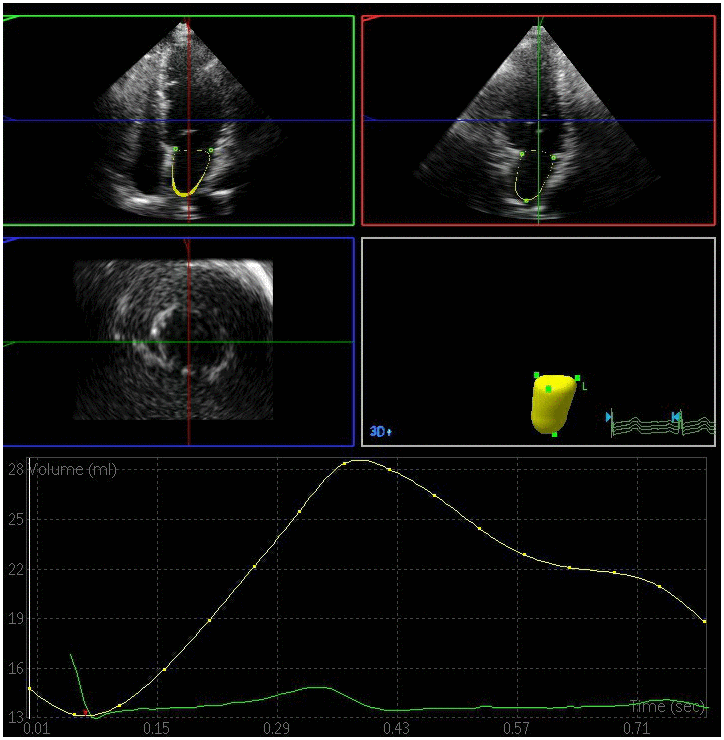

The left atrial maximum volume (LAVmax), left atrial pre-systolic volume (LAVp), and left atrial minimum volume (LAVmin) were significantly elevated in the DN and DM groups relative to the control group, whereas the total left atrial ejection fraction (LAEFt) and passive left atrial ejection fraction (LAEFp) were significantly lower in the DM and DN groups relative to the control group (P < 0.05) (Figures 1–3). The left atrial maximum volume index (LAVImax), left atrial pre-systolic volume index (LAVIp), and left atrial minimum volume index (LAVImin) were also significantly elevated in the DN group relative to the DM group, whereas the LAEFt and LAEFp parameters were significantly lower in the DN group relative to the DM group (P < 0.05). We also found that active left atrial ejection fraction (LAEFa) was significantly higher in the DN group relative to the DM and control groups (P < 0.05), whereas this parameter did not differ significantly between the DM and control groups (P > 0.05) (Table 3).

Figure 2. Left atrial volume quantification by RT-3DE of a case in DM group.